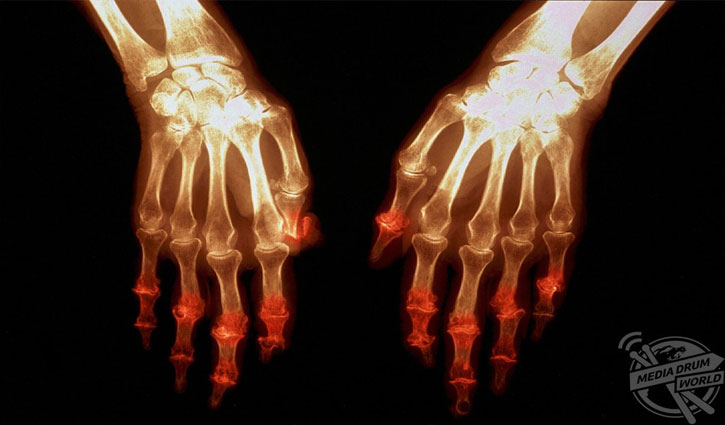

আর্থ্রাইটিসে আক্রান্ত একটি হাতের এক্স-রে। পৃথিবীতে প্রতি ১০০ জনে একজন আর্থ্রাইটিসে আক্রান্ত। সব বয়সীদের এই রোগে ভুগতে দেখা যায়। তবে ৪০ থেকে ৫০ বছর বয়সীদের এই রোগে বেশি ভুগতে দেখা যায়।